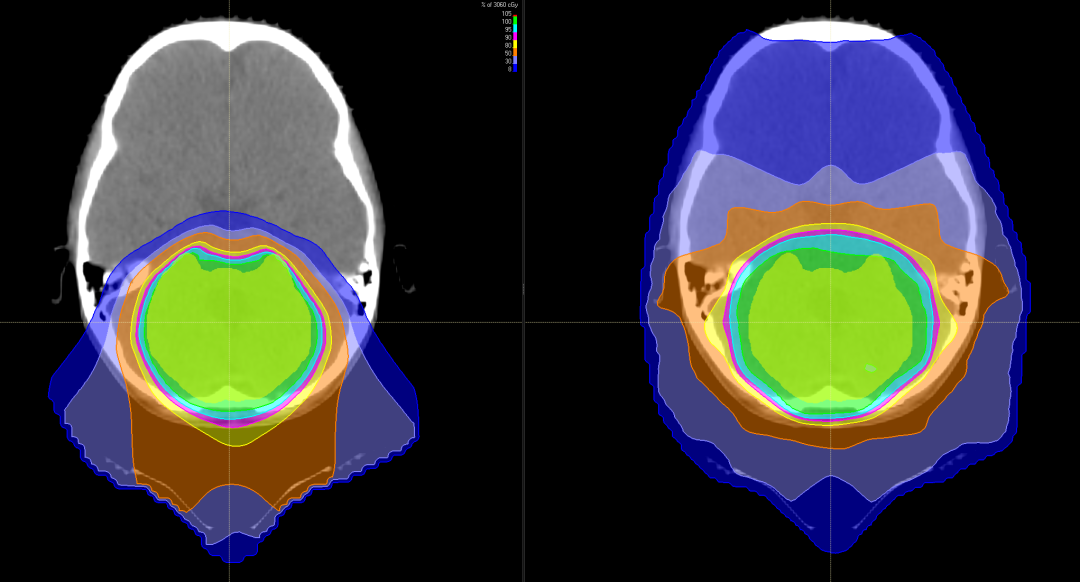

有研究表明,儿童神经母细胞瘤使用质子治疗的最大效益在于减少脑部正常组织构造的损伤,进而降低长期伤害。质子治疗是一种比其他任何形式的放射治疗更准确,更精确地靶向肿瘤,同时保留健康组织,目前全球最先进的一种放疗技术。通过质子治疗,可以最大限度地避免靶标外部的绝大多数不必要的辐射。

与传统形式的辐射相比,质子束会到达肿瘤内部的精准位置而不是沿着光束离开人体的路径释放大部分辐射剂量。实际上,质子没有肿瘤之外的辐射“退出剂量”,这意味着质子停在肿瘤上,不会继续伤害身体的健康部位。

对肿瘤周围组织损伤小不影响生长发育

随着儿童癌症治疗进步,儿童的存活率上升,存活下来的儿童患者日后之生活品质越来越受到关注,质子治疗具备能够减少散射剂量的优势,提升对肿瘤局部的控制,同时由于脑部神经组织多,易受辐射损害。质子治疗因具有布拉格峰的物理特性,使峰值部位对准肿瘤病灶处,发出最高剂量,产生最高峰,达到最佳杀瘤效果;峰后剂量趋于零,对周边脑组织几乎无影响。对于儿童脑瘤,可以避免有常规化疗引起的听力丧失、认知功能障碍、智力影响等。